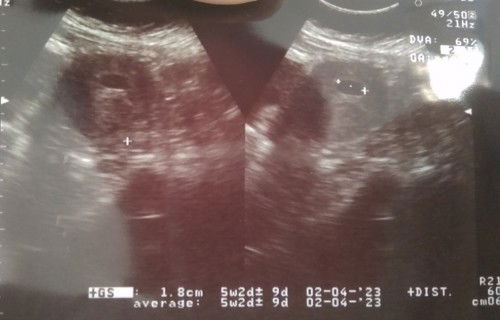

Hpht 8 Juni hrsnya masuk 7/8 week, kmrn 2/8 USG 5 week Baru kelihatan kantungnya, apa ada yang sama?

Ini persis yang aku rasain sekarang Bun....galau hpht 8w tp di USG baru 5w2d baru kelihatan kantong janinnya aja....dokter suruh balik sebulan lagi....semangat buat kita ya bund semoga tumbuh dengan baik Dede bayinya....Aamiin

Mom ini hasil Ugs pake usg biasa atau pakai transvaginal ya mom? saya juga baru check usg td pake usg biasa ga kelihatan apa apa, besok rujuk untuk usg lanjutan pakai transvaginal π₯Ί

Pakai USG 2d biasa mom, Bukan yg transvaginal, tp katanya Banyak yg bilang kalau transvaginal lebih jelas hasilnya